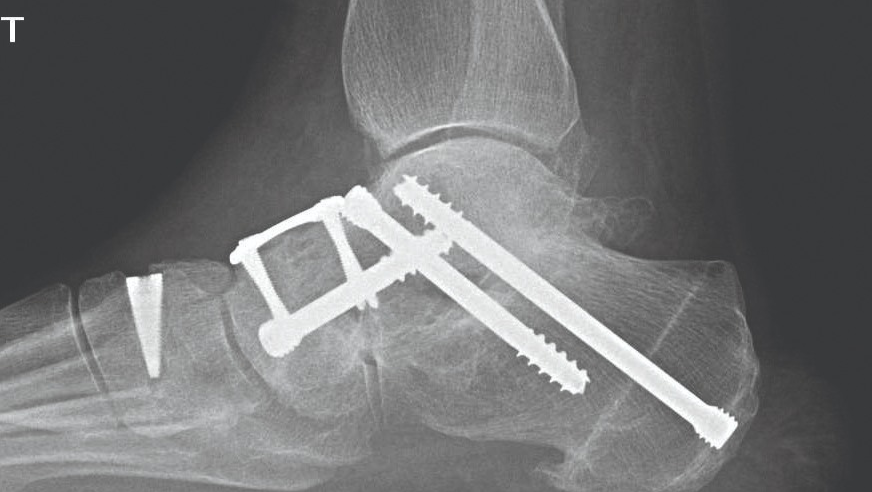

Stopa została zrekonstruowana przy użyciu metalowych śrub i prętów, ale z powodu błędów i opóźnień w systemie medycznym musiałam czekać aż 19 miesięcy na operację, żyjąc przez ten czas w ciągłym bólu i ograniczeniu ruchu.

Moja noga jest wypełniona metalem, a całe ciało musi nauczyć się stabilności i bezpiecznego poruszania się od nowa. Każda wpłata i każde udostępnienie tej zbiórki to dla mnie realna szansa na samodzielność, bezpieczeństwo i odzyskanie sprawności.

My health problems began in 2018 when I was involved in a serious car accident. Since then, I have been fighting to regain my health and mobility. Unfortunately, fate was not kind to me again in 2024, I suffered another very serious accident, in which I broke my right ankle in multiple places.

My foot was reconstructed using metal screws and rods, but due to errors and delays in the medical system, I had to wait 19 months for surgery, living all that time in constant pain and limited mobility.